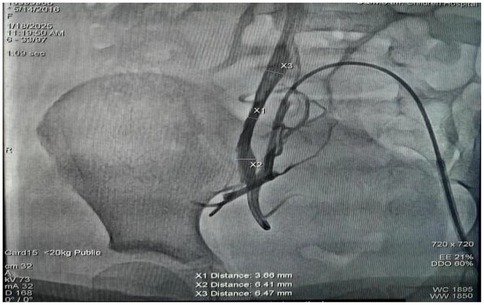

An 8.7-year-old female patient (weight: 25 kg) was admitted to our cardiovascular department with symptomatic pacemaker pocket infection. Her medical history included DM, retinal pigment abnormalities, progressive atrioventricular block culminating in a diagnosis of mitochondrial disease confirmed by mitochondrial DNA deletions. She had previously experienced cardiac syncope secondary to the complete atrioventricular block, necessitating conventional permanent pacemaker implantation. Post-implantation device testing confirmed appropriate pacemaker function with 100% right ventricular pacing. However, four months post-implantation, she developed a pacemaker pocket infection (Figure 1). Given her DM and the associated increased risk of recurrent infection, the entire pacemaker system was explanted. Permanent pacing remained clinically indicated due to progressive symptomatic atrioventricular block in the context of mitochondrial disease. Although re-implantation of a conventional transvenous pacemaker still carried significant infection risk, a leadless pacemaker offered a safer alternative with reduced infection potential. Preprocedural right femoral venography revealed a minimum vein diameter of 3.66 mm (Figure 2), which was insufficient for the 27-Fr introducer sheath required for femoral approach. However, the right internal jugular (RIJ) vein, with a minimum diameter of 6 mm, was deemed suitable for device implantation. After discussing the options for transvenous vs. leadless pacing system and alternative venous access sites with family, we proceeded with Aveir VR leadless pacemaker implantation via the RIJ approach.

Figure 2. Right femoral venography revealed a smallest diameter of 3.66 mm in the right femoral vein.

While femoral vein access remains the standard implantation route of Aveir VR, emerging evidence merits consideration of alternative approaches, particularly when femoral access is contraindicated or undesirable. Although current literature primarily describes internal jugular vein access in isolated case reports, this technique is supported by established safety profile of Micra implants via jugular access (17–19). In this case, the right femoral vein's critical luminal diameter (3.66 mm) was insufficient to accommodate the 27-Fr introducer sheath (25-Fr inner diameter), precluding femoral delivery. Consequently, the device was successfully deployed via an internal jugular venous approach following comprehensive preprocedural vascular mapping and real-time ultrasound-guided catheter navigation. The internal jugular venous approach offers an anatomically favorable trajectory for right atrial access due to its superoanterior orientation, which significantly shortens the intracardiac catheter pathway. This route eliminates navigation of the acute IVC-tricuspid angle while optimizing coaxial alignment with the ventricular septum for targeted deployment. Clinical data show significantly reduced mean procedure time, fluoroscopy time, and radiation dose compared to femoral access (14). However the movements to enter the right ventricular from the superior approach are opposite of those from the femoral vein, which may increase the challenge of achieving a safe implant and require meticulous torque control to counterbalance the inherent clockwise rotational forces during right ventricular engagement.